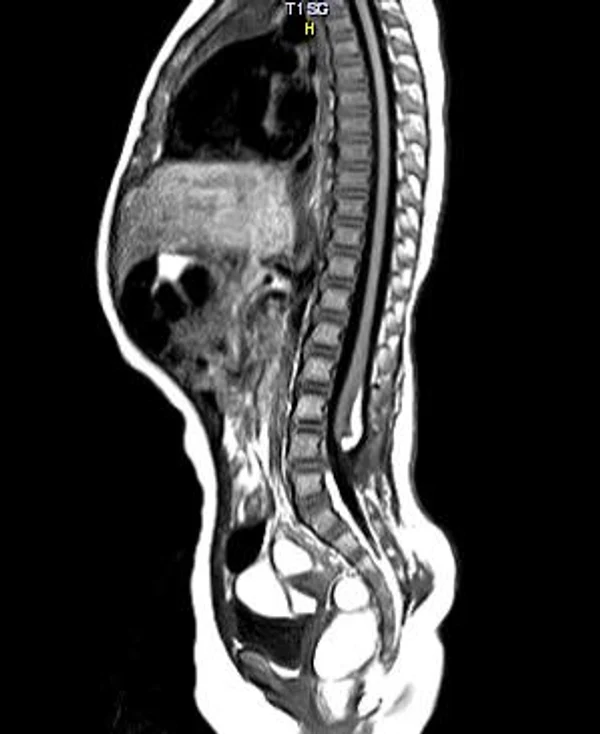

Spina bifida, спинно-мозговые грыжи, диастематомиелия, липоменингомиелолоцеле, фиксированный спинной мозгSpina bifida включают различные типы нарушения закладки и развития нервной трубки на спинальном уровне, что сопровождается незаращением дужек позвоночника и часто сопровождается одновременным пороком развития спинного мозга и его оболочек. Встречаются у 1 на 1000 – 3000 новорожденных. Могут наблюдаться в различных отделах позвоночника, но наиболее часто встречается в пояснично-крестцовом отделе. Незаращение дужек позвонков с наличием грыжевого выпячивания обозначается в литературе по разному: спинно-мозговые грыжи, spina bifida, spina bifida cystica, spina bifida vera, spina bifida typica, spina bifida aperta. Классификация spina bifida aperta: I Рахишизис. II Спинномозговые грыжи. Менингоцеле. Менингорадикулоцеле. Миеломенингоцеле. Миелоцистоцеле. Липоменингомиелоцеле. Основные сопутствующие пороки центральной нервной системы: Гидроцефалия до 65-85%. Аномалия Киари 2. Сирингомиелия.